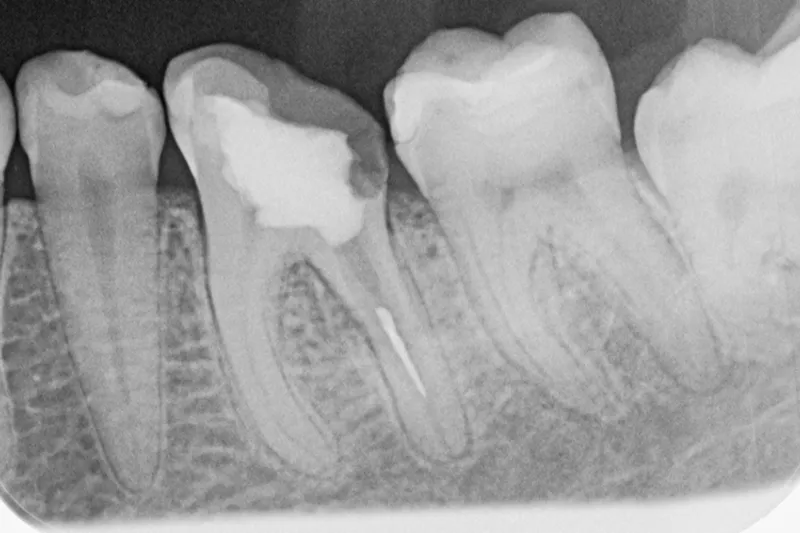

Knækket rodfil i distal kanal -6

Patienten henvender sig på klinikken pga. akutte smerter fra -6. Der laves akut oplukning og findes tre kanaler. Ved udrensning i distale kanal for at finde endeligt rodmål knækker ca. 1-2 mm af fil 08 i kanalen. Patienten bliver informeret og henvist til specialtandlæge for videre behandling.

Det fremgår, at der er tale om en filstørrelse 08, altså den tyndeste fil, der findes. Ved flerrodede tænder med lange, krumme og/eller oblitererede (“tilgroede”) rodkanaler er risikoen for filfraktur højere.